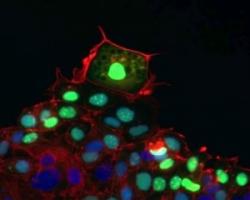

Actualité publiée il y a 10 années 3 moisCICATRISATION des PLAIES: Même chez les cellules il y a des leaders et des followers

Actualité publiée il y a 10 années 3 mois